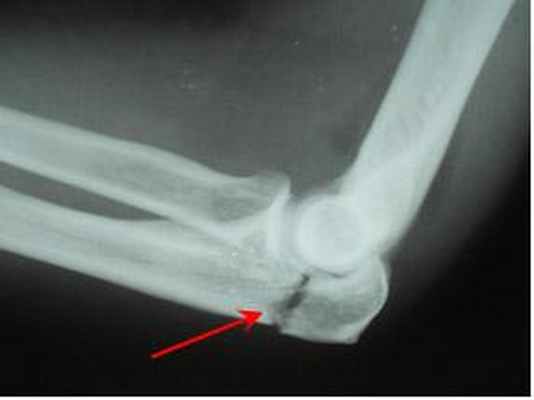

Довольно распространены также повреждения костей предплечья при которых происходит перелом одной из костей и вывих головки другой — это так называемые переломо-вывихи костей предплечья. Наиболее часто встречаются перелом Монтеджи (Monteggia 1814 г.) — перелом локтевой кости в сочетании с вывихом головки лучевой кости, и перелом Галеацци (Galeazzi) — перелом лучевой кости и вывих головки локтевой кости.

• Монтеджа возникает вследствие отражения удара согнутым и поднятым предплечьем, либо падения на прямую руку;

При переломе венечного отростка остеосинтез выполняют 3,5 мм винтом. Для остеосинтеза перелома головки лучевой кости применяют фиксацию малым спонгиозным винтом.

Остеосинтез головки лучевой кости и венечного отростка локтевой винтами.